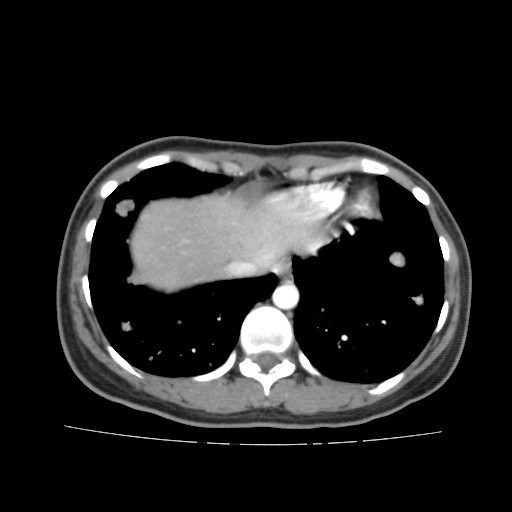

查体:右大腿上段较左侧增粗,后内侧皮下可触及大小约5*6cm肿物,质软,边界不清,活动度可,压痛(+),无波动感。 辅助检查:胸部CT:双肺多发转移瘤。

诊断:肺占位性病变(转移瘤?);大腿软组织疾患(右侧大腿肿物) 治疗:入院右下肢MR平扫+增强扫描:右侧大收肌软组织占位性病变,考虑间叶源性恶性肿瘤可能性大,血管源性可能?瘤周多发静脉曲张及侧枝循环形成,建议CT增强扫描进一步检查明确血管情况。遂于声引导下右大腿肿物穿刺活检,病理结果提示:(右大腿肿物)送检穿刺组织,肿瘤细胞形成器官样及腺泡状结构,细胞巢间为纤维性分隔,细胞呈大圆形、多边形,胞质丰富透亮,部分呈嗜伊红色,细胞核大,核分裂象少见,结合临床病史及免疫组化,考虑为腺泡状软组织肉瘤。免疫组化结果(①):CK(-),Vim(-),Ki-67(5%+),HMB45(-),MelanA(-),SMA(+),desmin(-),Myogenin(-),MyoD1(-),S100(-),NSE(部分+),CD56(-)。